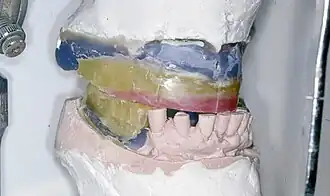

Einprobe

Nach der Aufstellung der Zähne in Wachs auf einer aus Wachs modellierten oder aus Kunststoff hergestellten Prothesenbasis durch den Zahntechniker erfolgt eine Einprobe der zahntechnischen Arbeit. Für den Behandlungsablauf existieren ebenso wie für das Aufstellen der Prothesenzähne verschiedene Lehrmeinungen, beispielsweise das Aufstellen nach Gysi, nach Gerber, nach Lerch, nach der APF-Methode (Ästhetik, Phonetik, Funktion), nach der TiF-Methode (Totalprothetik in Funktion), das AIl-OraI-Verfahren, die Methoden nach Gutowski oder nach Reusch.[19] In der Regel werden je Kiefer 14 Zähne ersetzt. Weisheitszähne werden nicht ersetzt. Nach mancher Lehrmeinung genügt der Ersatz von 12 Zähnen. Dabei bleiben die beiden zweiten Molaren (und die Weisheitszähne) nicht ersetzt. Bei der Einprobe kann die Kieferrelationsbestimmung und das Aussehen der Prothese durch Zahnarzt und Patient beurteilt und gegebenenfalls korrigiert werden. Oft ist nur ein Kompromiss unter den Anforderungen an Ästhetik, Phonetik und Funktion möglich, je nach anatomischer Ausgangslage.[21]

Die Kunststoffzähne sind auf einer Akrylplatte in Wachs aufgestellt.

Die Kunststoffzähne sind auf einer Akrylplatte in Wachs aufgestellt. -

Oberkiefer-Totalprothese aus Wachs auf dem Arbeitsmodell

Oberkiefer-Totalprothese aus Wachs auf dem Arbeitsmodell -

Oberkiefer-Totalprothesenbasis aus Wachs modelliert zur Einprobe